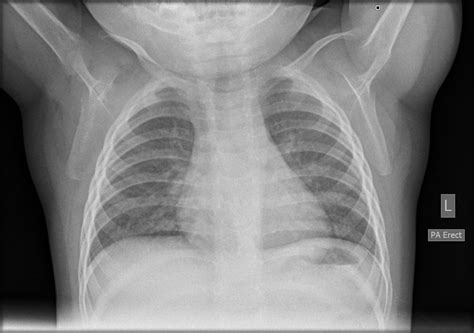

Normal Lung Xray

What Does a Normal Lung X-ray Look Like?

A normal lung X-ray typically shows clear lung fields with no signs of inflammation, infection, or other abnormalities. The lungs appear black due to the air they contain, while the heart and other structures appear white. The diaphragm, the muscle that separates the chest from the abdomen, is visible as a curved line at the bottom of the lungs. The ribs and spine are also clearly visible.

Here are some key features of a normal lung X-ray:

• Clear lung fields with no opacities or infiltrates.

• Visible heart and mediastinal structures.

• Clear costophrenic angles (the areas where the ribs meet the diaphragm).

• No signs of pleural effusion (fluid around the lungs).

• Normal appearance of the trachea and bronchi.